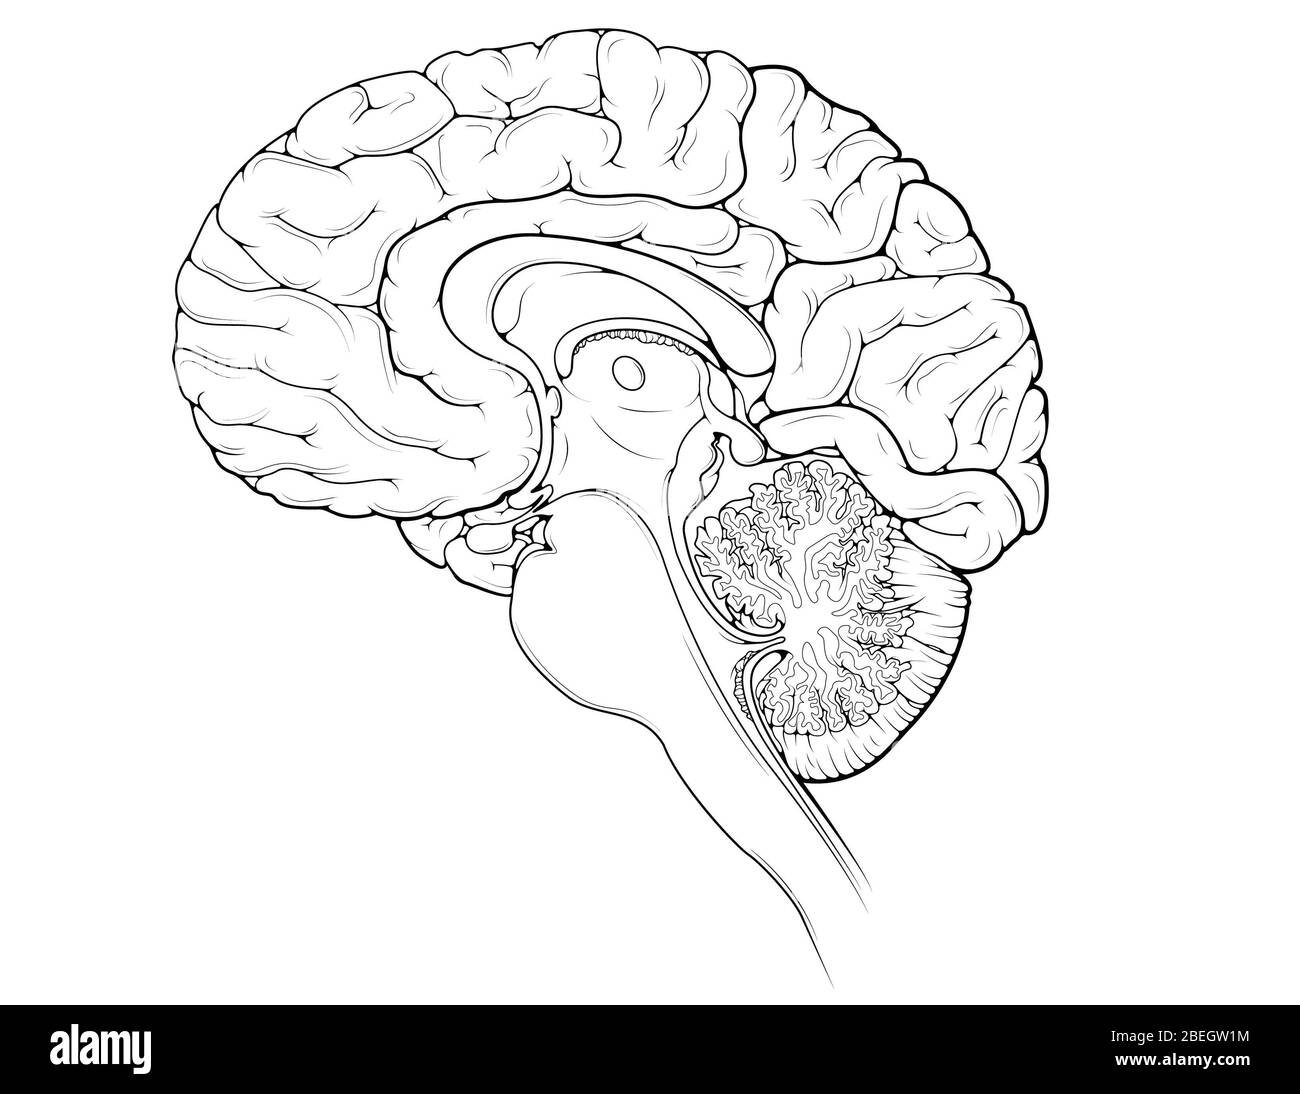

RMBCE641–Sagittale Abschnitt des menschlichen Gehirns, Darstellung von Strukturen der zerebralen Ventrikel, Kleinhirn und Hirnstamm.